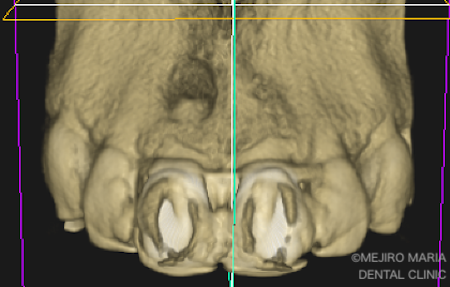

歯根端切除術開始後、右上1番の歯の根尖切断面を確認すると、凹状に切削されていました。

さらにマイクロスコープにて、根尖方向から根管内を確認すると、感染物と思われる歯科用充填剤が残留していました(2枚目写真の矢印)。これが、今回の根尖性歯周炎の原因であると考えられます。